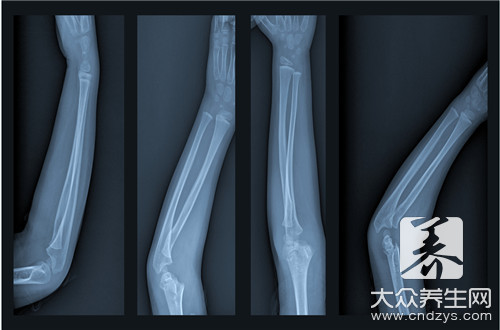

骨折是指骨结构的连续性完全或部分断裂。多见于儿童及老年人,中青年人也时有发生。病人常为—个部位骨折,少数为多发性骨折。经及时恰当处理,多数病人能恢复原来的功能,少数病人可遗留有不同程度的后遗症。

骨折病人的典型表现是伤后出现局部变形、肢体等出现异常运动、移动肢体时可听到骨擦音。此外,伤口剧痛,局部肿胀、淤血,伤后出现运动障碍。

2.固定

骨折复位后,因不稳定,容易发生再移位,因此要采用不同的方法将其固定在满意的位置,使其逐渐愈合。常用的固定方法有:小夹板、石膏绷带、外固定支架、牵引制动固定等,这些固定方法称外固定。如果通过手术切开用钢板、钢针、髓内针、螺丝钉等固定,则称内固定。